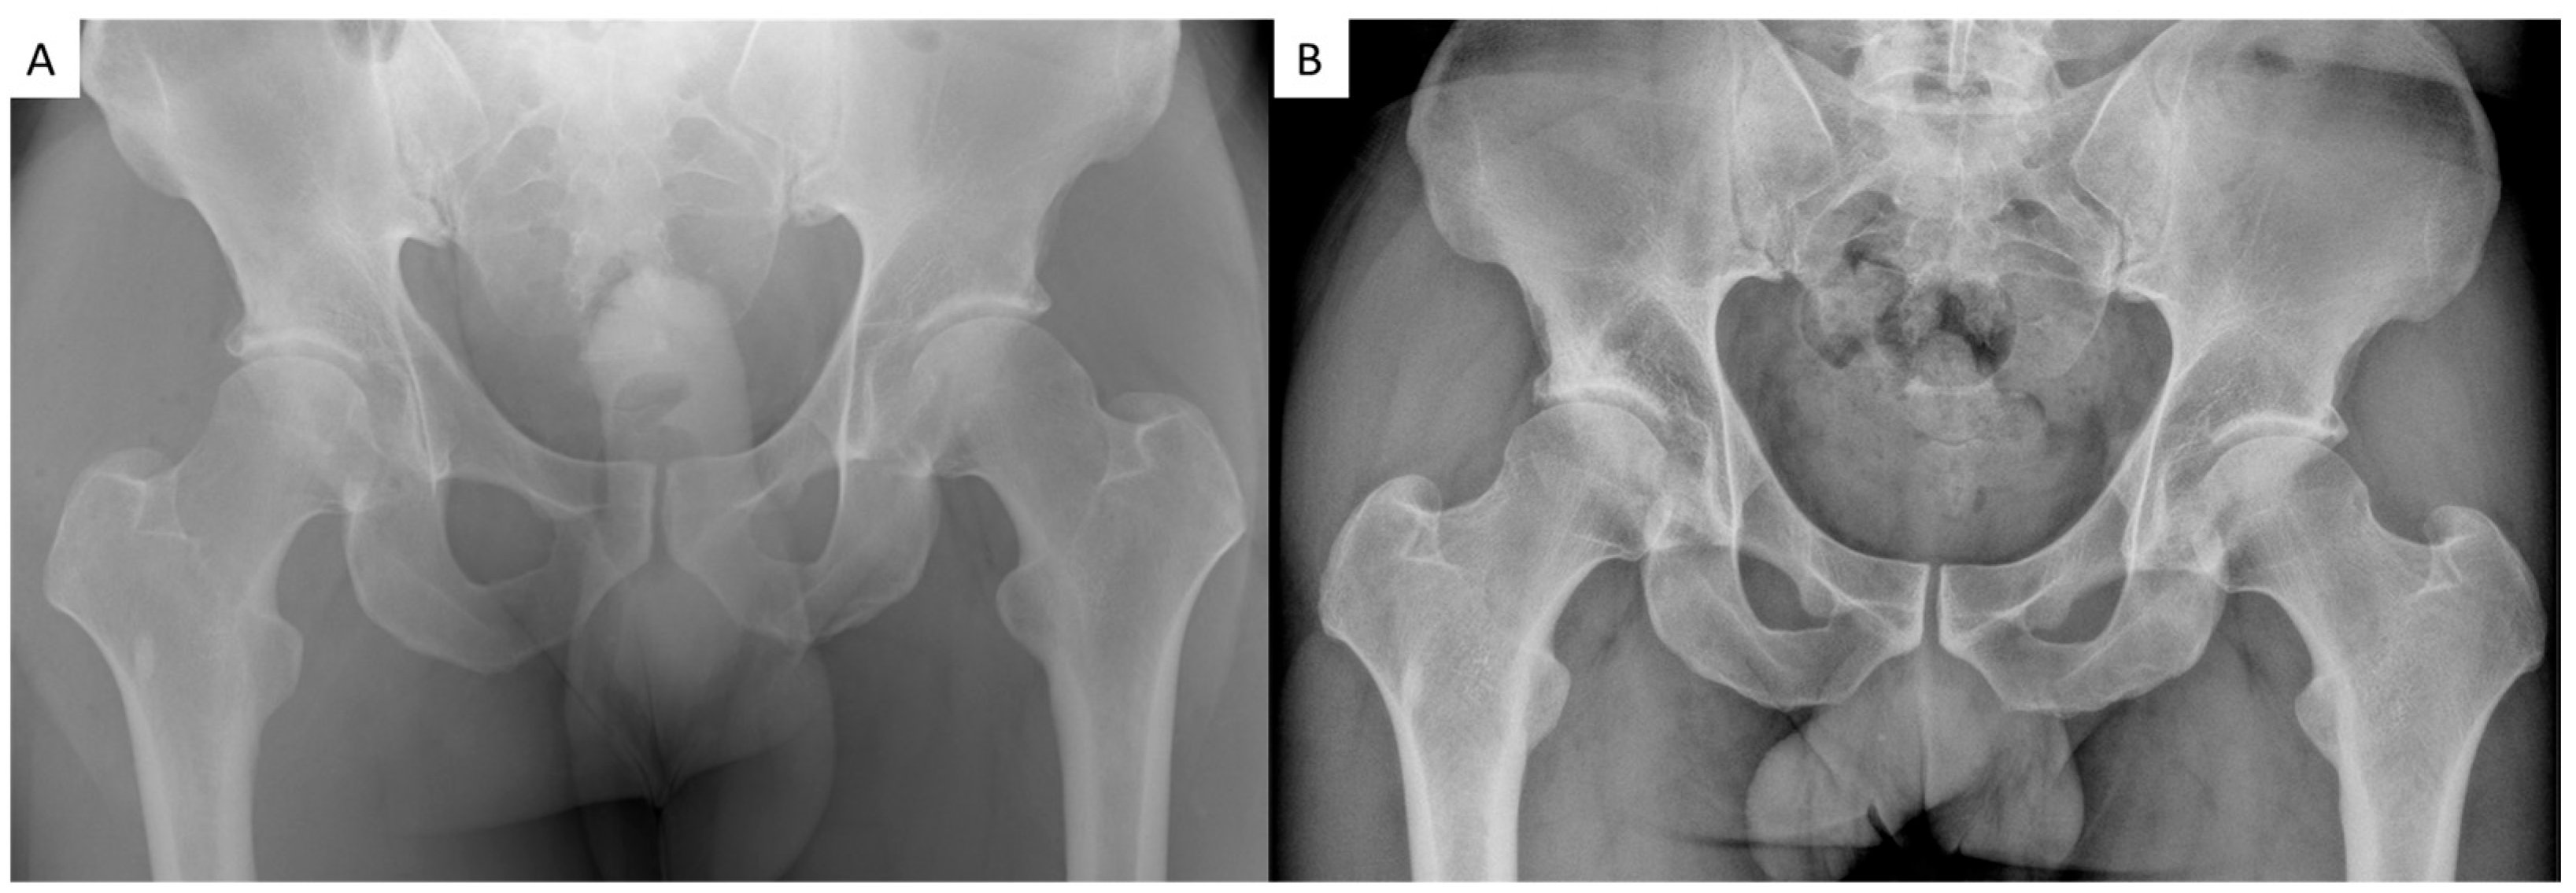

3.4. Radiographic Outcomes